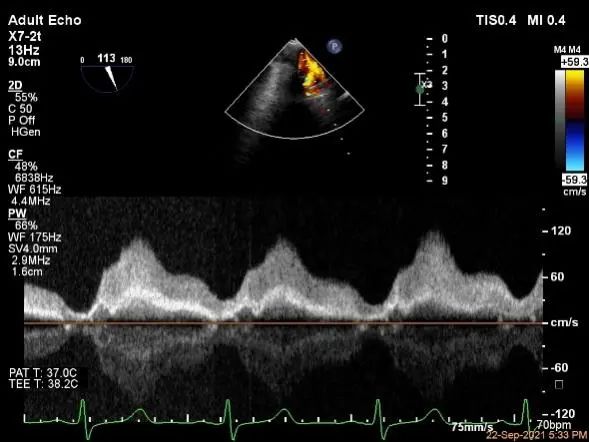

评估二尖瓣瓣口平均跨瓣压差:1mmHg

肺静脉血流频谱恢复正常

MVA:7.8cm2,平均跨瓣压差:1mmHg